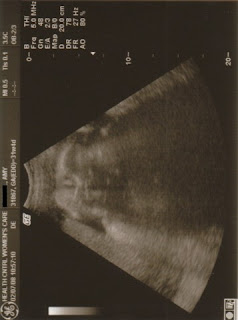

I had my 32 week appointment last Thursday, and everything continues to look great! My doctor had me go in for an ultrasound to check Baby's measurements and for a weight estimate. They measured the head, belly, and femur, and everything was in the 40th - 50th percentiles. The doctor is estimating that Baby will be in the 7 pound range at full-term, so not too big or too small. This is one area where we are happy to be completely average! I'm still feeling really good, other than being more tired and having a little trouble sleeping - definitely minor stuff. Baby also continues to have a nice strong heartbeat - around 145. We are so blessed that everything has gone so smoothly!

Here are a few sonogram pictures. The first one is of Baby's face, straight on. The second one has labels! The third picture is a profile, and you can see both hands. I can't wait to see our little one in person and finally be able to hold him or her!!!